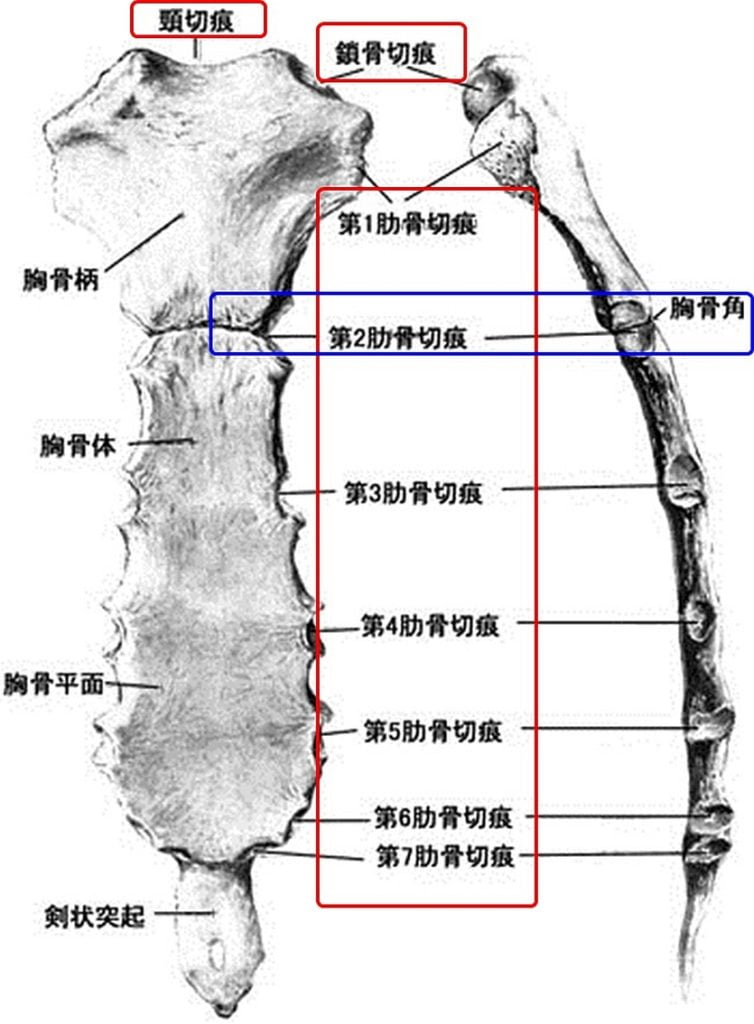

分析出来る事は,相手の肋骨の直下,つまり,みぞおちの上の骨,

"剣状突起部位"と自分の"ひざの皿"が当たったのではと推測しています。

もしくは,

この予想は考えたくないですが,

相手の”浮遊肋骨"部=肋骨の最下部

と自分の膝が当たった可能性も否定は出来ない。

そうなると相手側が"骨折"した可能性が高い。

"浮遊肋骨"という左右2対の肋骨の場所は

胸骨に接しずに浮いているため,

強い外力が及ぶと"折れやすい"のです。